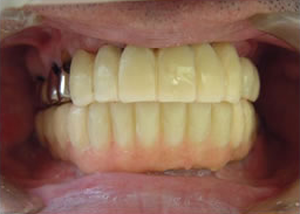

19.下は作った最終本物の歯が入りました。

これで治療終了。

開口器を入れた口元

治療完了

平成21年1月29日

(治療期間:1年7ヶ月)